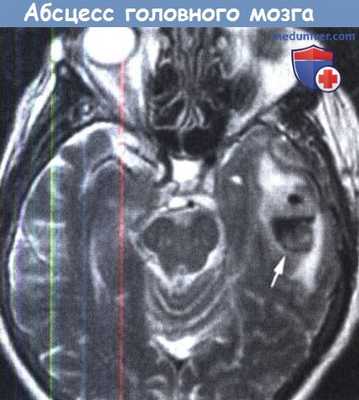

Хорошо инкапсулированный абсцесс головного мозга,

являющийся осложнением среднего отита.

в) Компьютерная томография. КТ является очень полезной в оценке пациента с подозрением на отогенный абсцесс головного мозга. Сканирование обеспечивает раннее выявление абсцессов и улучшение результатов. Абсцесс головного мозга выглядит как гипоин-тенсивная зона, окруженная областью отека, такая конфигурация, известна как признак «кольца». Для оценки эффектов лечения, определения срока хирургического вмешательства может быть рекомендована серия КТ-исследований

МРТ также оказалась полезной и превосходит КТ в выявлении тонких изменений в паренхиме головного мозга и в выявлении распространения абсцесса в субарахноидальное пространство или в желудочек.